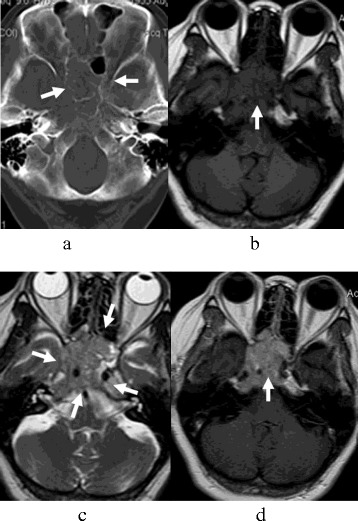

The lesions were located in the bilateral sphenoid sinus (n = 9, Figure 1), ethmoidal sinus (n = 6, Figure 2), and maxillary sinus (n = 4). All lesions showed a symmetry or ‘pigeon’ pattern in the bilateral sphenoid sinus (Figure 1).

Figure 1.

SNEC of paranasal sinuses in a 41-year-old man (a-d). The lesion was symmetrical, and the size was about 5.8 cm × 5.7 cm × 4.3 cm. (a) CT image showed worm-eaten bone destruction in sphenoid sinus, anterior cranial fossa, and orbital apex; however, bone contours still could be seen. (b) T1-weighted MR image demonstrated isointensity. (c) T2-weighted MR image demonstrated isointense together with a ‘pigeon’ pattern. (d) Contrast-enhanced T1-weighted MR image demonstrated a moderate heterogeneous enhancement mass, which showed involvement of the pharyngonasal cavity, orbital apex, pterygopalatine fossa, sella, cavernous sinus, internal carotid canal, and jugular foramen.